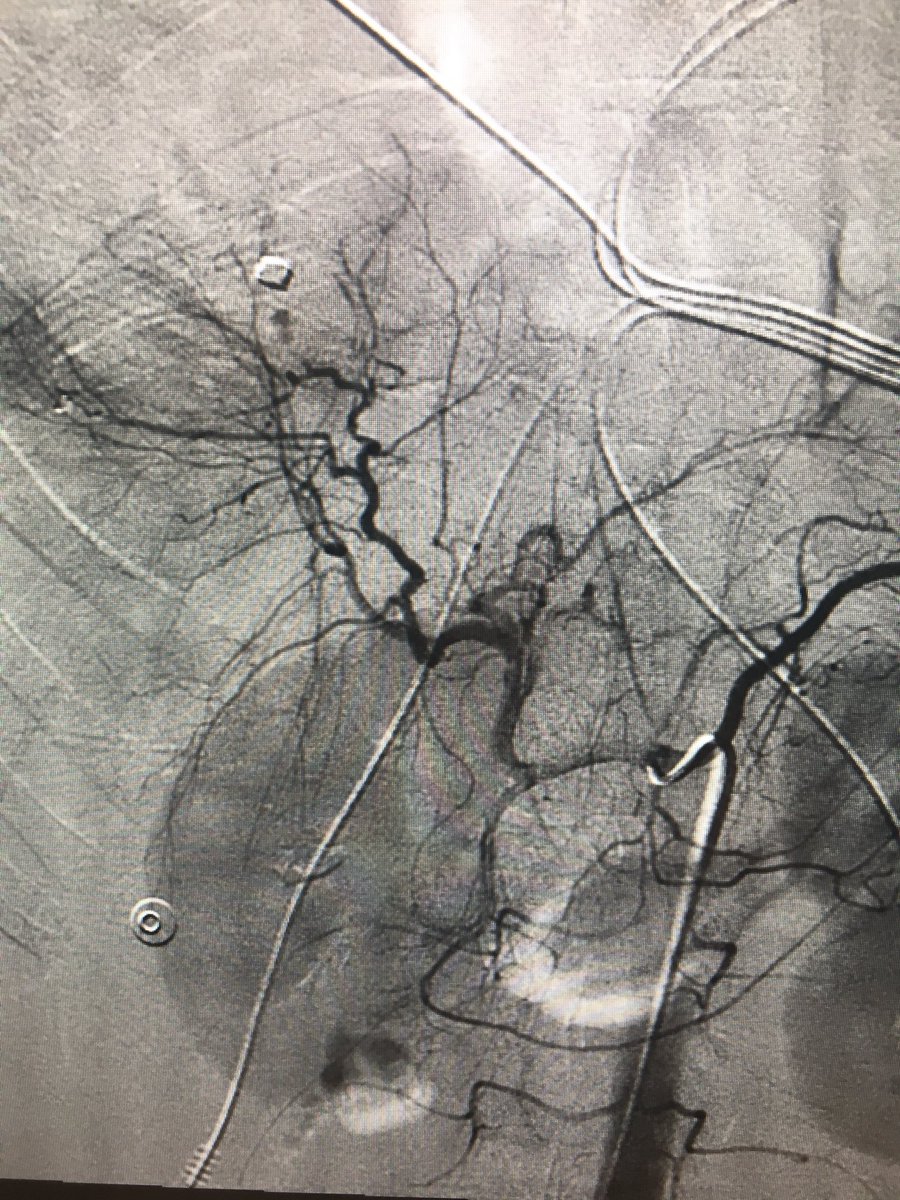

Renal pseudoaneurysm embo after MVA Saturday, proximal splenic artery embo after fall on Sunday, liver embo after GSW tonight...can’t wait to see what Tuesday brings! #withoutascalpel #womeninIR #IRad @Priddy_IR @Chando_RadMD @UofLRadiology